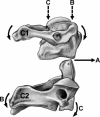

Data synthesis: Research on normal kinematics and minor and major injury mechanisms to the cervical spine reveals the complex nature of movement in this segment. The movement into a single plane is not the product of equal and summative movement between and among all cervical vertebrae. Instead, individual vertebrae may experience a reversal of motion while traveling through a single plane of movement. Furthermore, vertebral movement in 1 plane often requires contributed movement in 1 or 2 other planes. Injury mechanisms are even more complex. The reaction of the cervical spine to an axial-load impact has been investigated using cadaver specimens and demonstrates a buckling effect. Impact location and head orientation affect the degree and level of resultant injury.